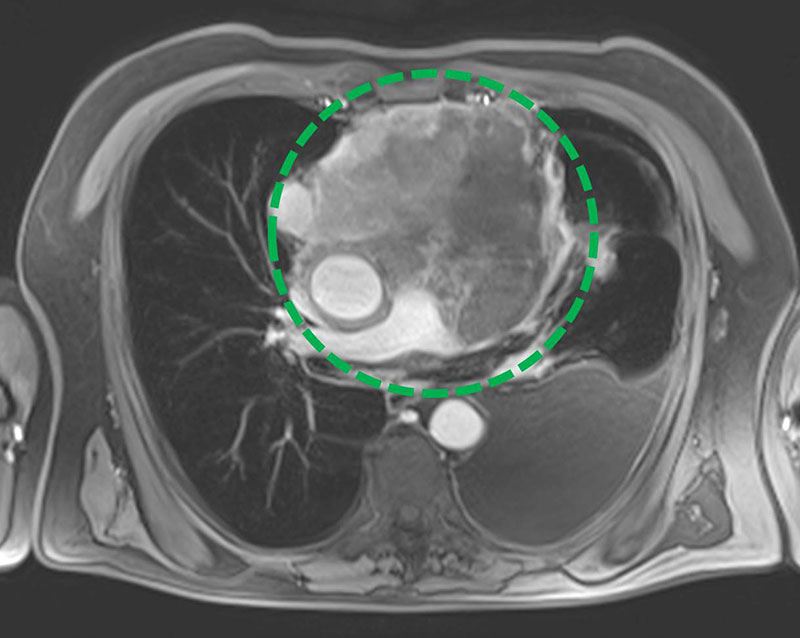

3. Magnetresonanztomografie ("MRT")

Deutlich später als CT und Röntgen hat sich die MRT in der Lungendiagnostik etabliert. Sie ist aufwändiger als andere Verfahren, bietet aber viele Vorteile – allen voran die Möglichkeit, Aufnahmen der Lunge ohne Röntgenstrahlung zu erhalten. Bei der MRT liegt der Patient in einem starken Magnetfeld, in dem die Wasserstoffatome des Körpers mit einem feinen Radiowellen-Impuls so angeregt werden, dass sie ein schwaches Signal senden. Dieses wird von den Antennen des Gerätes aufgenommen und für die Berechnung der Aufnahmen verwendet. Hierbei erscheinen wasserhaltige Anteile des Körpers (Leber, Muskeln) hell und wasserarme Anteile (auch die Lunge) dunkler. Krankhafte (pathologische) Veränderungen der Lunge mit einer Neubildung von Gewebe (Tumor) oder mit Einlagerung von Flüssigkeiten (bei einer Lungenentzündung oder bei Herzinsuffizienz) kommen hell vor dem dunklen Hintergrund des Lungengewebes zur Darstellung. Die MRT ist zudem hervorragend geeignet, die Weichteile der Thoraxwand sowie des Mediastinums zu beurteilen. In allen Fällen, in denen eine Strahlenexposition vermieden werden soll oder muss – z.B. zur Untersuchung von Kindern oder Schwangeren – bietet die MRT eine wertvolle Alternative. Die Radiologie Darmstadt bietet als erstes privates Röntgeninstitut die MRT der Lunge als Routineverfahren an. Hierzu stehen an mehreren Standorten hochmoderne MR-Tomographen bereit.

Thoraxtumor im MRT

(Zum Vergrößern bitte anklicken)